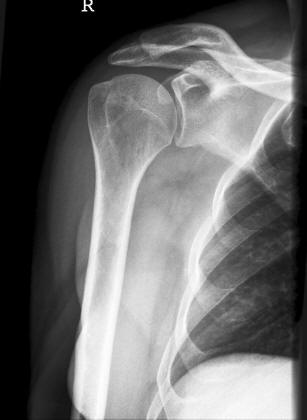

Schulter seitlich

SchulterY.jpg

Fehler

Bei dieser Aufnahme wurde der Patient zu weit gedreht, dass somit der Oberarm in den Rippen verschwunden ist. Zudem scheint der Patient einen Buckel gemacht zu haben.

Abhilfe

Abhilfe bringt erstens den Patienten aufrechter hinzusetzen; den Arm richtig lagern, sprich Hand auf dem Bauch und zweitens auf die Drehung von 45° beim Patienten zu achten.